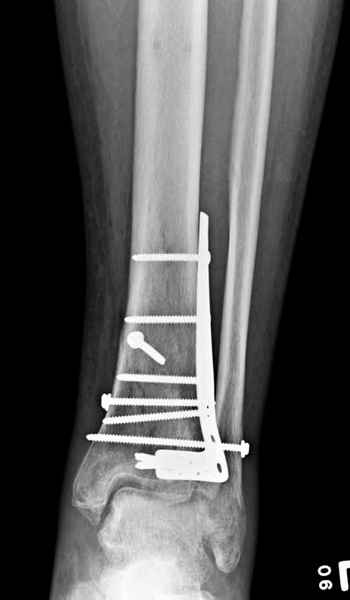

Публикации за последние пять лет показывают, что в лечении переломов

пилона важным является состояние мягких тканей. Поэтому при лечении

пилона, особенно после высокоэнергетической травмы, необходимо

придерживаться правила - лучше проводить запоздалую фиксацию, чем после

операции иметь проблемы с мягкотканными осложнениями.

Закрытый метод фиксации рекомендуется, когда фрагменты были сопоставлены

в результате лигаментотаксиса, а открытый минимальный метод при

нерепонированных отломках.

После репозиции сустава необходимо удостовериться

в заполнении образовавшейся полости ауто- или синтетическими

заполнителями, что в последующем предохраняет от варусного коллапса.

Фиксация наружной лодыжки подсказывается переломом, а малоберцовая

является ключом-ориентиром для длины конечности.

Любая фиксация - преконтурированные пластины с уголовой стабильностью,

медиальная, латеральная в зависимости от нахождения отломков или

наружная фиксация типа аппарата Илизарова подходят для ранней мобилизации.

Не все переломы пилона фиксируются медиальной

пластиной,  поэтому, учитывая что большой фрагмент

находится на латеральной стороне, я бы применил

передне-латеральную пластину.